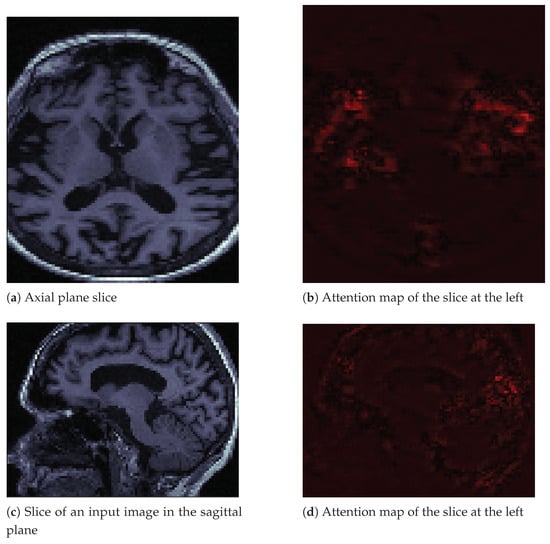

Attention maps are visual tools that explain deep convolutional neural networks [33]. We used the M3d-Cam tool [34] with the Guided Gradient-weighted Class Activation Mapping (Grad-CAM) algorithm. We generated new images through M3d-CAM, and with these images, we could interpret what the neural network was emphasizing to make a decision. For example, in Figure 6a, we can see an image in the axial plane of a person with Alzheimer’s disease. We extracted only one slice of the cuboid. To its right, in Figure 6b, we can see that the neural network focuses its attention on brain atrophy. We extracted the same slice number from the attention map cuboid. In Figure 6c,d, we see the same patient and the same features in the sagittal plane. We also only extracted one slice of that plane.

Figure 6.

Input image slices and their attention maps from an MRI of a patient with AD.

In the images in Figure 6, we can see how brain atrophy areas appear more prominent. We noticed this behavior in other images for which we produced attention maps. The behavior of the network was as expected in terms of identifying the regions of importance. However, we also noticed that sometimes the neural network gave importance to bony areas of the skull or even to areas outside the skull. In other words, the attention maps seemed to have a potential function as debugging tools. Besides, they allowed us to propose solutions. We believe that we must improve the preprocessing of images by removing the skull using a mask, as the skull is a potential source of noise. This background noise could explain some of the classifier’s inaccurate results, as observed in the confusion matrices. The neural network may be learning uninformative features or patterns as a result of excess inputs. We could improve the results and reduce the inaccurate results by providing the CNN with only brain images, thus removing potential artifacts associated with the skull.

Additionally, we include the attention map for a non-affected individual in Figure 7 on page 14. The difference from the image in Figure 6 is that this image seems to generate less attention from the neural network. We observed the same behavior in other images of healthy people.

Figure 7.

Image slices and their attention maps from an MRI of a healthy person.